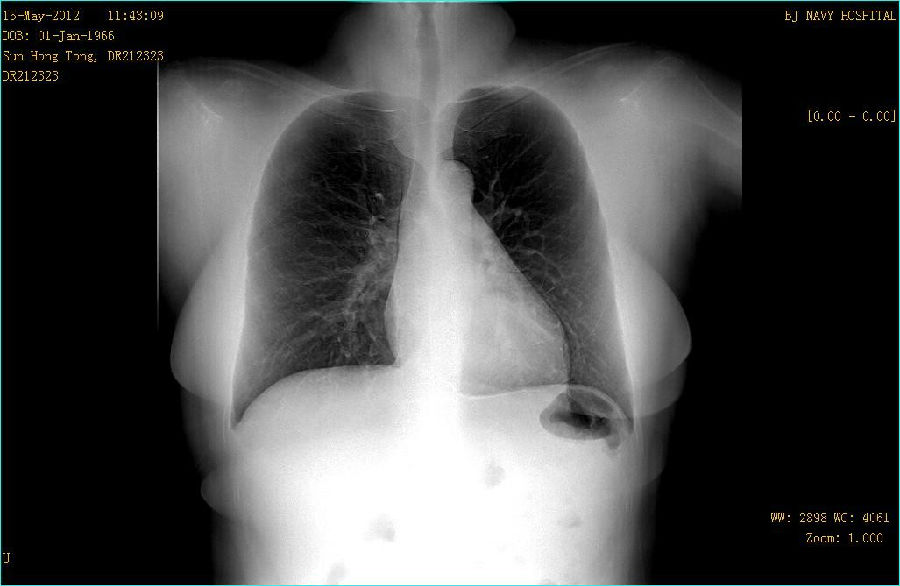

病史: M,46Y 病人主诉:常规体检 曝光参数 120KV;194mA ; 25ms ; 0.284mGy 常规胸部平片: